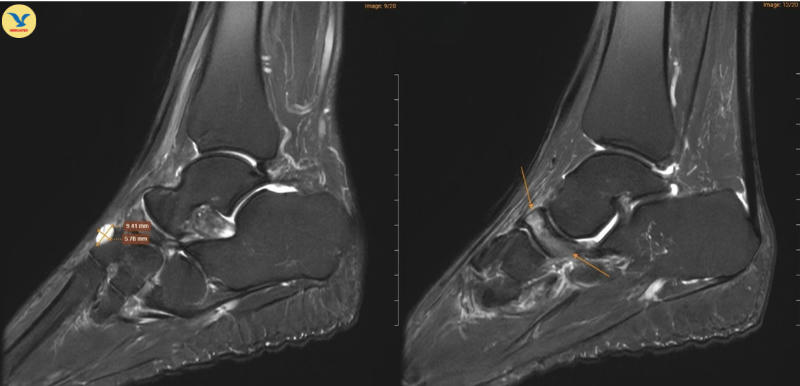

Tại MEDLATEC, bác sĩ đã chỉ định chụp Cộng hưởng từ (MRI) để tìm kiếm những tổn thương sâu trong cấu trúc xương. Trên lát cắt Sagittal T1W, hình ảnh cho thấy xương ghe bị xẹp và biến dạng điển hình hình dấu phẩy, kèm theo tình trạng đặc xương dưới sụn. Trên chuỗi xung T2W FS, ghi nhận tình trạng phù tủy xương ghe rõ rệt.

Đồng thời ghi nhận hình ảnh tổn thương gai xương thoái hóa khớp cổ chân trái, ổ phù tủy xương vị trí xương sên, phù nề dây chằng chày mác sau, dây chằng sên mác sau, dây chằng gót chày và dây chằng tam giác cổ chân, dịch khớp cổ chân, phù nề phần mềm quanh khớp cổ chân.

Dựa trên sự phối hợp chặt chẽ giữa lâm sàng và chẩn đoán hình ảnh, chị H. được chẩn đoán theo dõi Hội chứng Muller-Weiss ở chân phải, phù tủy xương sên trái.